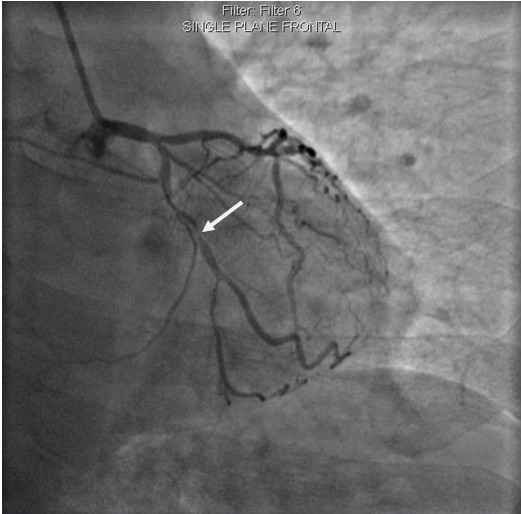

李先生蜘蛛位術(shù)前影像

術(shù)前,翟光耀主任還親自為李先生復(fù)查冠狀動脈造影,造影結(jié)果顯示:患者的前降支、回旋支、右冠等冠脈三支嚴(yán)重病變、嚴(yán)重鈣化,且均為彌漫性長病變,最重處99%以上管腔極嚴(yán)重狹窄。翟主任仔細(xì)閱讀造影結(jié)果后指出:結(jié)合李先生的實際情況,雖然微創(chuàng)介入手術(shù)難度比較大,但仍可行;李先生心臟三支主干動脈均存在極其嚴(yán)重的狹窄,每一支動脈均至少植入2-3枚支架,根據(jù)患者的耐受情況,李先生可能需要分3次分別對三支動脈進行介入手術(shù);考慮到李先生路途遙遠(yuǎn),病情嚴(yán)重,不宜反復(fù)奔波,并且患者迫切要求能夠徹 底解決病痛,在病情允許的情況下,如果手術(shù)順利,爭取為患者進行“一站式”手術(shù),一 次 性解決全部三支動脈病變!

手術(shù)方案確定之后,在心血管內(nèi)三科趙景新主任、介入醫(yī)學(xué)科富孝晨主任的配合下,翟光耀主任親自擔(dān)任主刀,分別依次對李先生的三支動脈進行了完全血運重建。由于手術(shù)進展順利,李先生術(shù)中沒有任何癥狀,耐受良好,于是成功的將三支動脈“一站式”治療!術(shù)中,由于李先生左主干遠(yuǎn)端分叉處存在嚴(yán)重病變,翟光耀主任選擇國際指南推薦的DK-mini-Crush技術(shù),確保了分叉處兩支主干開口均萬無一失。據(jù)悉,DK-mini-Crush技術(shù)是目前冠脈分叉病變領(lǐng)域最為復(fù)雜及難以掌握的介入技術(shù)之一,對手術(shù)醫(yī)生經(jīng)驗、體力均提出了極大的挑戰(zhàn)。極為擅長復(fù)雜介入技術(shù)的翟光耀主任卻用嫻熟的技術(shù)確保了李先生手術(shù)的成功。